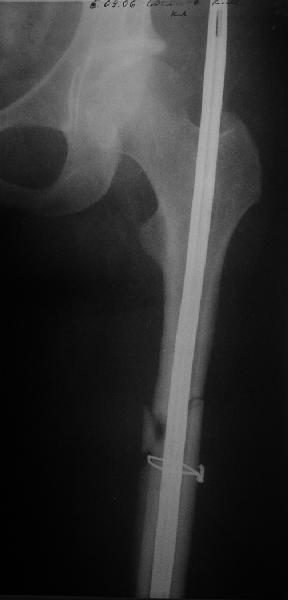

Пациент попал под наше наблюдение через 3 недели после первого остеосинтеза (фото 1). Учитывая, нестабильность остеосинтеза, выстоящий стержень закрыто перештифтовали (фото 2), через 3 месяца динамизация. К 5 месяцам имели укорочение 2 см, при том, что динамический винт стал статическим. От дальнейшей динамизации отказались, учитывая наличие контакта между фрагментами и возможность прогрессирования укорочения. К 1,5 года сращение не достигнуто (фото 3). Удалили гвоздь, выполнили дистракционный остеосинтез с целью стимуляции остеогенеза и компенсации укорочения (фото 4), потом закрыто перештифтовали после рассверливания (фото 5). На сегодняшний день, через 4 месяца после последней операции (фото 6) признаков регенерата нет, длина восстановлена, ходит без дополнительной опоры.